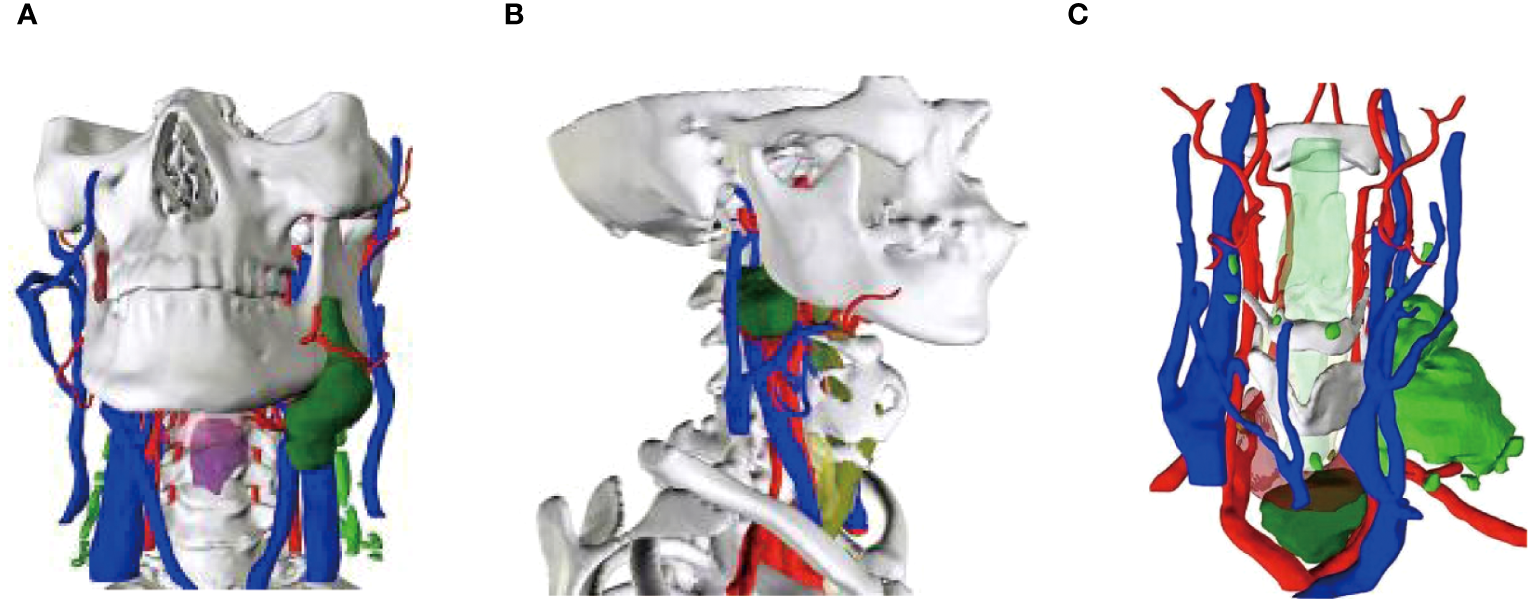

A 56-year-old female underwent surgery for ameloblastoma in the left mandible 2 years previously. Specialist examination revealed that the patient had swelling on the left face and neoplasm in the area surrounding the left mandibular angle and ramus, approximately 5.0 × 4.0 cm measuring in size. The patient also had a mild limitation in mouth opening, and 36, 37, and 38 were not detected in the oral cavity. According to the patient’s previous medical records and consultation report from the pathology department of our hospital, the pathological diagnosis of the patient was confirmed as ameloblastoma (Figure 1). The patient was diagnosed with ameloblastoma upon admission and scheduled to undergo partial mandibular resection and fibular osteocutaneous flap repair. She underwent CTA examination of the maxillofacial and the left calf prior to surgery. The obtained CTA data were imported into a software workstation for 3D reconstruction and subsequently downloaded onto a holographic display (Figures 2, 3). During the operation, the left calf was automatically positioned according to the holographic display, and the perforator vessels were dissected in real-time (Figure 4). Fibular osteocutaneous flaps were prepared to repair the mandible, and direct sutures were placed at the donor site (Figures 5, 6). After the operation, the flap fully survived, and during the 6-month follow-up, the patient expressed satisfaction with the reconstructive outcome.

After applying MR technology in the field of orthopedics, Lee et al. (26) demonstrated that displaying the anatomical structure of skin-covered areas aids surgeons in rapid localization during screw placement and reduces surgical risks, thus improving surgical accuracy. Shi et al. (27) were the first to apply MR technology in hepatectomy and achieved accurate matching between a 3D hologram model and the target organs. Thus, MR technology can be combined with other clinical treatment techniques. For example, when combined with a da Vinci robotic system, it can minimize trauma and surgical complications while achieving the goal of curing lesions (28, 29). Although MR technology has been applied in orthopedics, hepatobiliary surgery, and neurosurgery (30–32), there are relatively few reports on its application in the field of oral and maxillofacial surgery (33–35). Therefore, in the early stages of the study, the author first attempted to apply MR technology to clinical teaching and doctor-patient communication, which achieved good results and accumulated rich experience (Figure 7). In this study, we used MR technology to perform 3D reconstruction of the maxillofacial region in 40 patients with malignant oral tumors. We found that the reconstructed 3D models were accurate and intuitive, and could be overlaid on the surgical site in real time with high precision. Compared to traditional imaging techniques, MR technology allows for easier understanding of organ anatomy, tumor shape, and location and expands the previously limited view of maxillofacial surgery in terms of depth and breadth, reducing judgment time and mental workload. In this study, the 3D reconstruction of the mandible in five patients was more distinct in terms of three-dimensional sense and boundary level compared to the reconstruction of soft tissues (Figure 8).

Figure 8

Mixed reality technology to rebuild the primary focus. (A) Buccal mucosa carcinoma reconstruction; (B) Oropharyngeal carcinoma reconstruction; (C) Thyroid malignancy reconstruction.